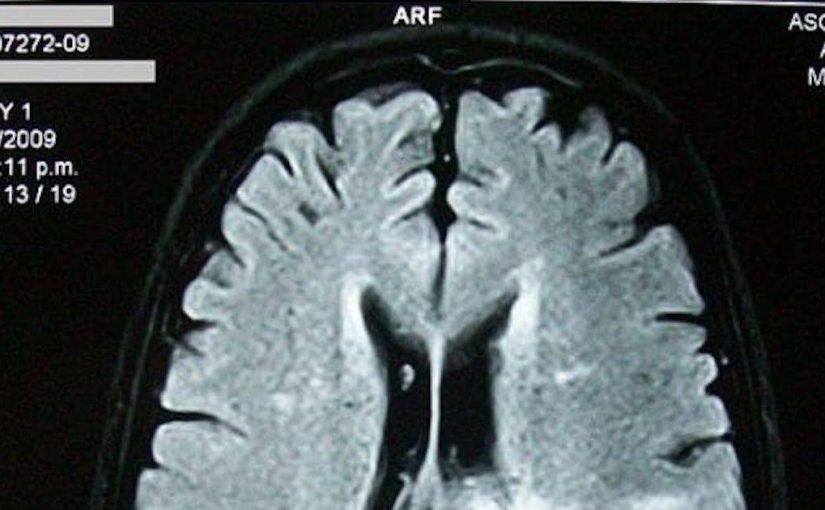

הרופא דחק בו להגיע לבית החולים "מיד" לצורך בדיקת MRI שחשפה גוש בגזע המוח שלו – רגע שהעביר גל של פחד גם בו וגם באמו, סונורה סוורדס.

מכיוון שהמשאבים הנוירוכירורגיים בסיואקס סיטי היו מוגבלים, ג'ונס הועבר לבית החולים 'מרסי', שם בוצע MRI נוסף ואפשרות לניתוח נדונה בתחילה. עם זאת, חוסר הוודאות לגבי מיקום הגידול ומיקומו הרגיש ליד גזע המוח הובילו את הרופאים להפנות אותו למתקן באומהה לצורך בדיקות הדמיה מתקדמות יותר.

"ואז זה היה הרגע שבו הם אמרו לי שיש גידול של 2 סנטימטרים בתוך גזע המוח שלי," אמר ג'ונס. "הוא התמזג עם קירות גזע המוח שלי."

למרות האתגרים, הביופסיה אישרה שג'ונס סובל מגליומה דיפוזית של קו האמצע (DMG), סרטן מוח נדיר ואגרסיבי הידוע בעמידותו לטיפולים, כזה שלא ניתן להפריד אותו מהרקמה הסובבת.